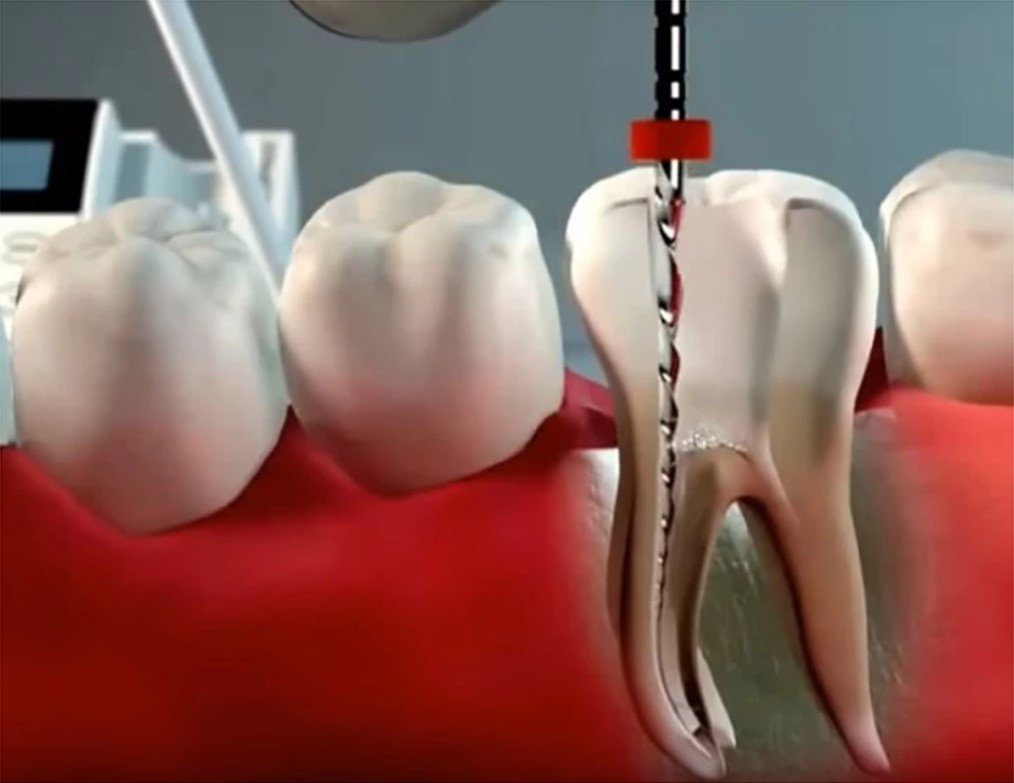

Usamos limas específicas que alargam os canais radiculares até 0,06mm de diâmetro.

Limpeza e Modelagem Interna: Com o dente anestesiado, o profissional acessa a câmara pulpar. Ferramentas finíssimas, as limas endodônticas, entram em ação para remover todo o tecido inflamado ou infectado. Elas também ajudam a alargar e modelar os canais radiculares, preparando o terreno para a desinfecção.

O Processo de Limpeza: O dentista utiliza instrumentos específicos para limpar e desinfetar os canais radiculares. A remoção do tecido doente e a desinfecção são etapas cruciais para eliminar a infecção e prevenir problemas futuros. É um trabalho minucioso de higienização interna.

Irrigação Inteligente: A irrigação contínua durante o preparo do canal garante que a solução desinfetante alcance todas as áreas. Técnicas modernas e instrumentos ultrassônicos potencializam a ação desses líquidos, garantindo uma limpeza profunda e completa.